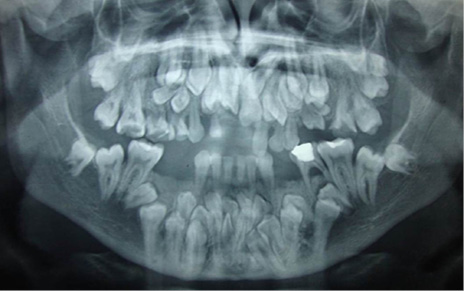

En el estudio imagenológico se observó en la radiografía de tórax, hipoplasia clavicular bilateral y tórax en forma de campana (Figura 2), en la radiografía panorámica se mostró la presencia de once dientes supernumerarios en el maxilar y nueve en la mandíbula (Figura 3), en la radiografía lateral cráneo se observó presencia de huesos wormianos landoideos (Figura 4); en la radiografía carpal se observó longitud simétrica de las falanges y sin alteraciones (Figura 5), de acuerdo con los hallazgos encontrados en el examen físico y la evaluación radiológica, se realizó la impresión diagnóstica de displasia cleidocraneal.

Figura 3. Radiografía panorámica en donde se revela la presencia de múltiples dientes supernumerarios. Fuente: autores.